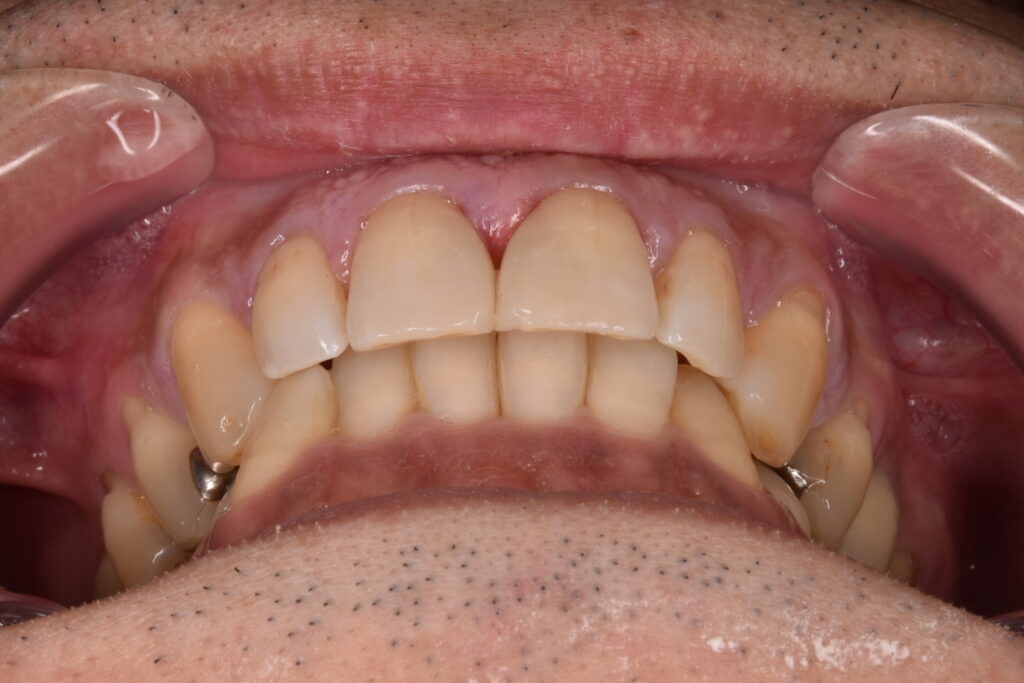

50代男性です。当院にご相談してくださる前に他院で前歯2本のダイレクトボンディング?を受けられたそうです。前歯2本の隙間は確かに白いレジンで埋められていましたが、本当に盛って作っただけのもので、違和感がかなり強かったそうです。

施術前

当院でタイレクトボンディング2歯のやりかえをご希望されて、2本でご契約してくださいました。他院のレジンは前日に取れたそうです。

約2時間後です。

治療前とは比べ物にならないほど自然だと大変喜んでくだいました。歯のもっこり感もなくちゃんとフロスも通ります。